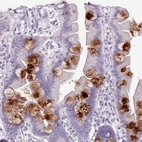

Immunohistochemical staining of human small intestine shows strong cytoplasmic positivity in goblet cells.